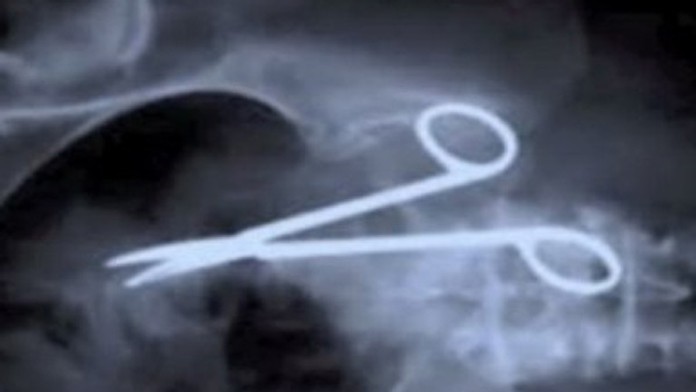

Lekári zabudli mužovi 12 centimetrov dlhú svorku v bruchu

Deväť rokov trápili Alena Papaca bolesti brucha, s ktorými si lekári v Mostare nevedeli rady. Liečili ho na všetko možné, vrátane zápalu pankreasu, nič ale nepomáhalo, napísal bosniansky denník Dnevni list. Príčinu ťažkostí odhalilo až vyšetrenie pľúc na počítačovom tomografe, kam Papaca poslali kvôli chronickému kašľu.

Na monitore sa totiž objavila aj 12 centimetrov dlhá svorka, ktorú lekári zabudli v jeho útrobách pri operácii žalúdočného vredu.

Práve nástroj zvaný klieštiky, pripomínajúci nožnice, ktoré sa používajú na zastavenie krvácania, pacientovi tlačili na pľúca a stále ho nútili ku kašľu. Svorka ale hlavne dlhých deväť rokov spôsobovala Alenovi bolesti brucha, s ktorými bol dokonca niekoľkokrát hospitalizovaný. "Prvýkrát ma brucho začalo silno bolieť rok po operácii," zveril sa dnes tridsaťosemročný muž, ktorému ale lekári nevedeli pomôcť. Vyšetrovali ho totiž len s pomocou ultrazvuku a na ňom si nikto zabudnutého nástroja nevšimol.